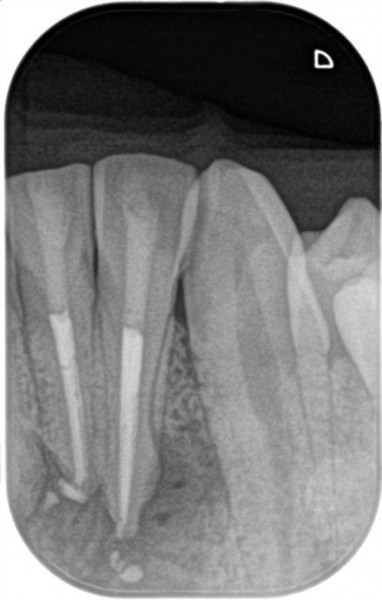

来院時には下顎は大きく腫れ、初診時のレントゲン写真(右側写真)ではレントゲンフィルムに収まりきらないほど病変が増大しており、確認のために撮影したC T画像(左側写真)では隣在歯(隣の歯)にまで及ぶ病変が骨を溶かしているのが確認できました。

初診時の検査では歯根破折の所見は確認できず、根管治療ならび予後不良時には歯根端切除術を行うことでマネージメントできると判断し治療を開始しました。